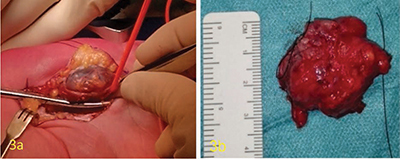

教学要点:血管网状肌瘤在磁共振成像上的表现为外周 T1 和 T2 高密度边缘、邻近的迂曲血管结构和暗网状征象。

Teaching point: Angioleiomyoma is defined on MR by a peripheral T1- and T2-hypointense rim, adjacent tortuous vascular structures, and a dark reticular sign.